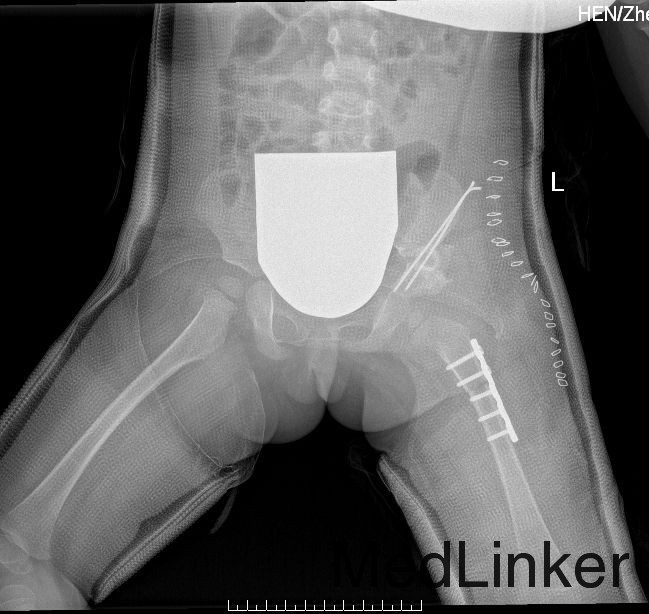

西医诊断:左侧发育性髋关节脱位 治疗:全麻下行“左髋切复、股内收肌松解、Salter骨盆截骨、股骨上段旋转截骨内固定并植骨术”

1、院外避免外伤,避免剧烈运动,避免下地负重; 2、院外继续治疗,适时换药、拆线,避免感染; 3、院外继续左侧全长、右侧半长髋人字石膏外固定;